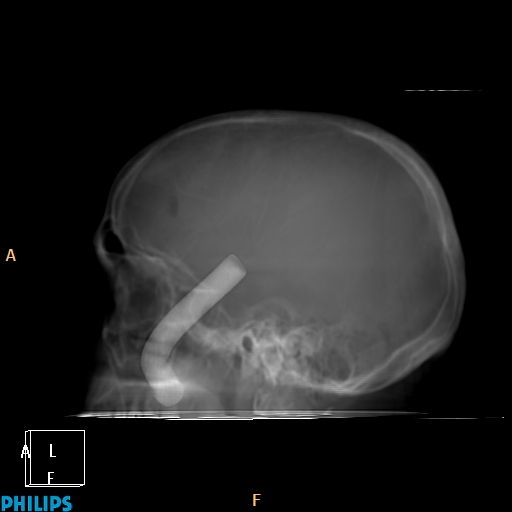

Accident de travail, chute sur une barre de fer. La barre de fer a été coupé sur le chantier pour dégager le patient A noter, comme on peut le voir sur la dernière image, que le patient était conscient et réveillé